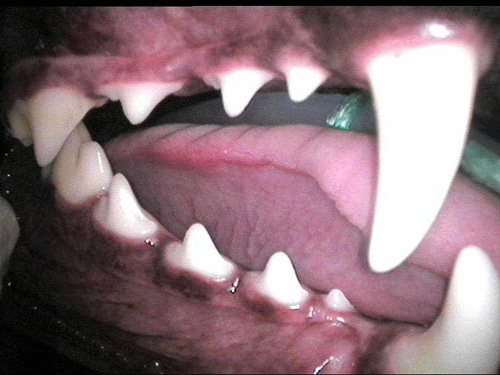

cat perio 2,5

Dent tartar 1-5